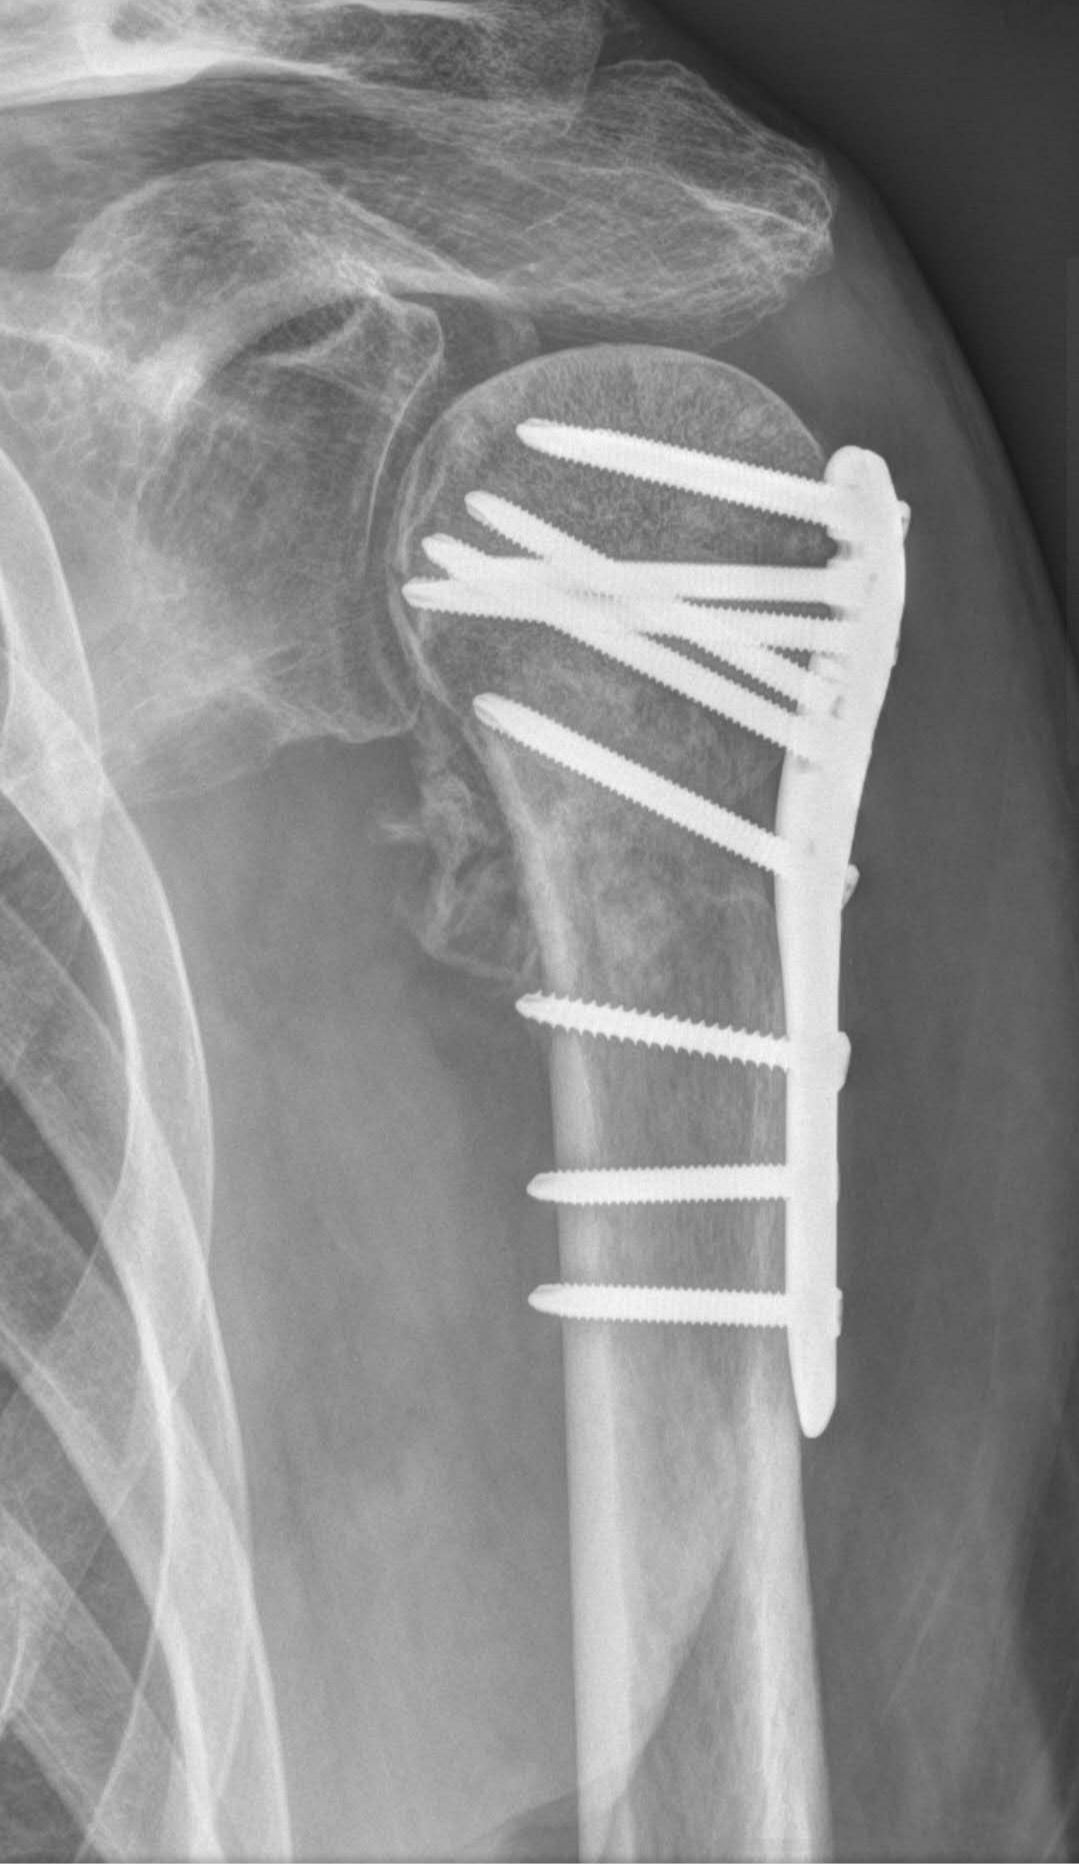

還記得那天閒聊時,我關心問:「闊別四年多啦B哥,你好嗎?」對方沉寂良久後曰:「還可以,就是忙進出醫院。一週物理治療五天,下月中需進院把臂內金屬支架取走。沒事,日子還得要過。」嗯,B哥向來積極樂觀,屬俠客類性情中人;可從他這分享,頓感其無奈黯然。他遂補來手臂X光照,看得我五味雜陳。唉,健壯身軀植入冰冷金屬。心頭一凜,話接不上來。草草道別後,七上八落的心無處安放。我是否該說些什麼?但西方老外多循傳統醫療,介入可好?放下交托吧、全然交托自得引領。抱頭睡去看如何……

了解後得悉一回交通意外,B哥左臂植入金屬支架,臂膀不時隱隱作痛。持續物理治療後加針灸仍未見好轉。兩年來受盡疼痛折磨,夜不成眠。再好的脾氣也耐不住揪心之痛。心頭大計與項目無限延期。人,像丟了魂,恁也不起勁。B哥聊得動容,男友已準備就緒。拿講義解析過後,直接動手。B哥先來數個手臂伸展的疼痛示範,男友已了知其「開關」在哪,二話不說就地一按。哎呀,再強B哥也叫出聲來。一下、兩下、三下,男友信心滿滿曰:「試試再伸展看如何?」只見他扭曲面容瞬間鬆綁,久違笑容脠開來。B哥激動著:「嘩,怎會這樣?兩年多手一轉即咔咔作響;如今竟順了,一陣風通了過去般!這究竟是什麼?」我笑搶話:「手臂大開關,跟抽油煙機開關……同理。」